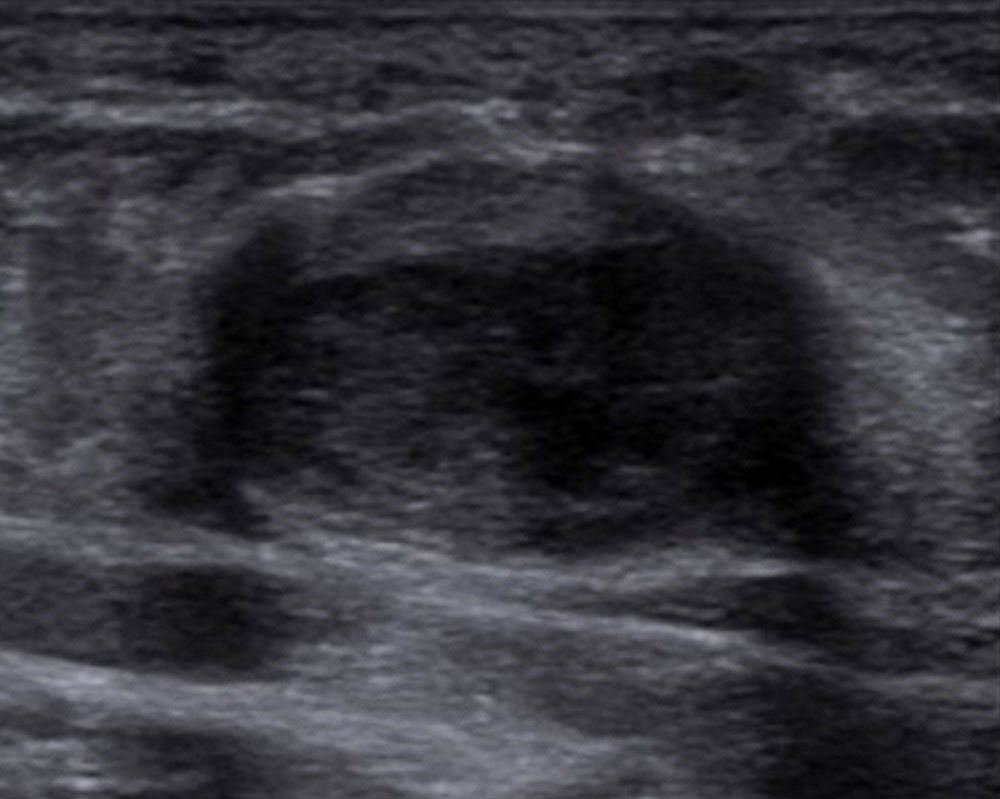

The most important imaging to detect or exclude phlebothrombosis is sonography. The affected vein section shows the thrombus contained in the vessel lumen, which cannot be compressed by compressing the vein with the transducer. Depending on age, this vascular thrombus tends to have a relatively low echogenicity initially in acute cases. The vein diameter is significantly increased by the intraluminal thrombus in the acute phase. In color-coded duplex sonography (CCDS), no color signal is found in the vein owing to the lack of blood flow, even at very low PRF settings (low pulse repetition frequency PRF = high detection sensitivity for flowing blood). With increasing thrombus age, the thrombus shrinks in size and becomes increasingly echogenic. In the further course, at least partial recanalization of the thrombosed vein occurs in favorable cases. Often beginning at the vein wall, blood (echo-free on ultrasound) again flows through the vessel surrounding the thrombus.